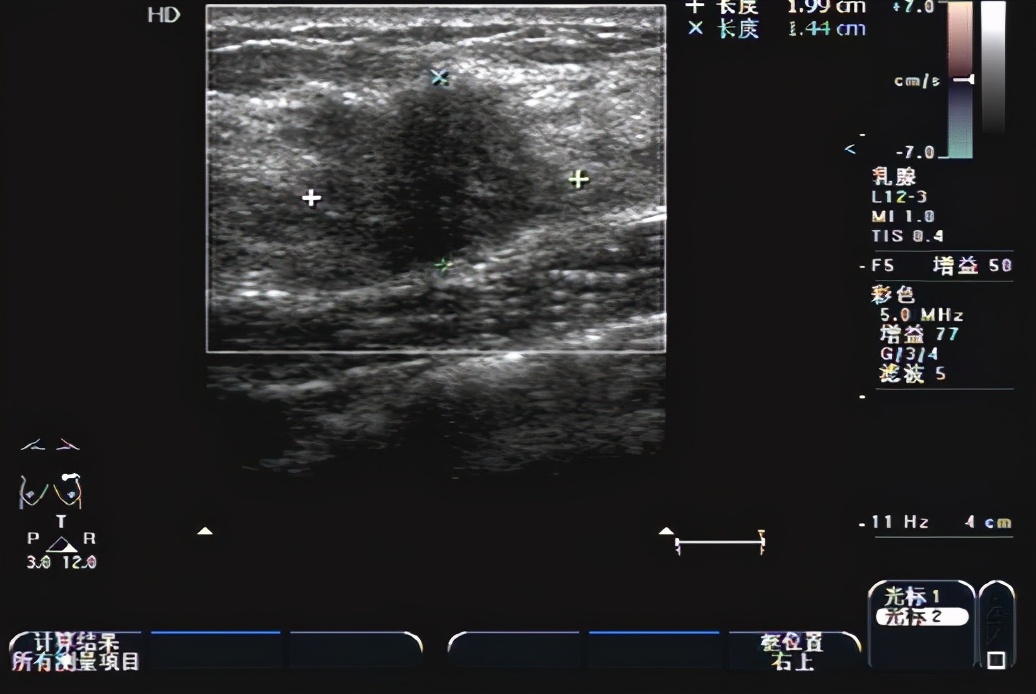

B超发现了我左乳中可疑的结节 | 作者供图

我机械地从医生手里接过B超结果,走出检查室,找到一个沙发坐了下来。脑袋嗡嗡作响,我暗示自己,不会那么糟糕的,估计是个纤维瘤啥的。给结果单拍照时,我发现自己的两只手都在抖。